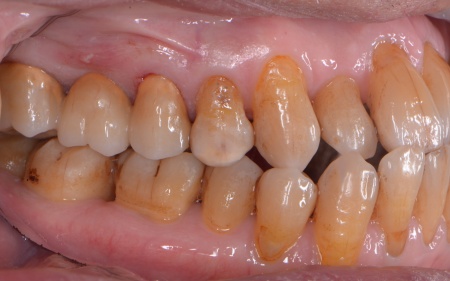

①MTA歯髄温存療法(神経を残す治療) ②根管治療(神経を取る治療) 患者様は「歯を長持ちさせたい」との希望から、①MTA歯髄温存療法を選択されました。 まずブリッジを慎重に取り外し、虫歯を確認します。 数週間後、しみたり痛んだりする症状は認められず、コールドテストとバイタルテストでも歯の神経が問題なく機能している状態であると判断できました。 神経が温存できていることを確認できたため精密な型取りを行い、虫歯の再発リスクが低く強度も高いセラミックのジルコニアでブリッジを新たに作製しました。 |